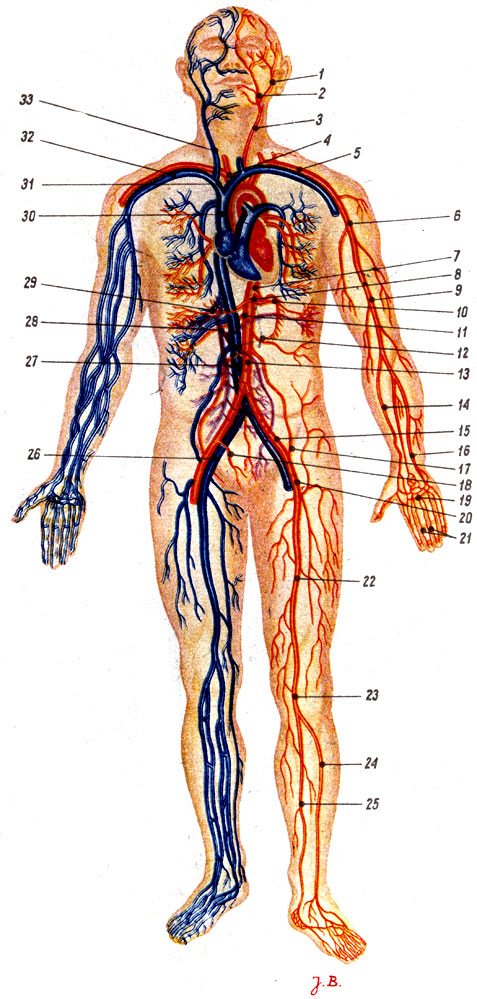

Кровеносная система человека: структура и функции

Раздел: Идеи и советы